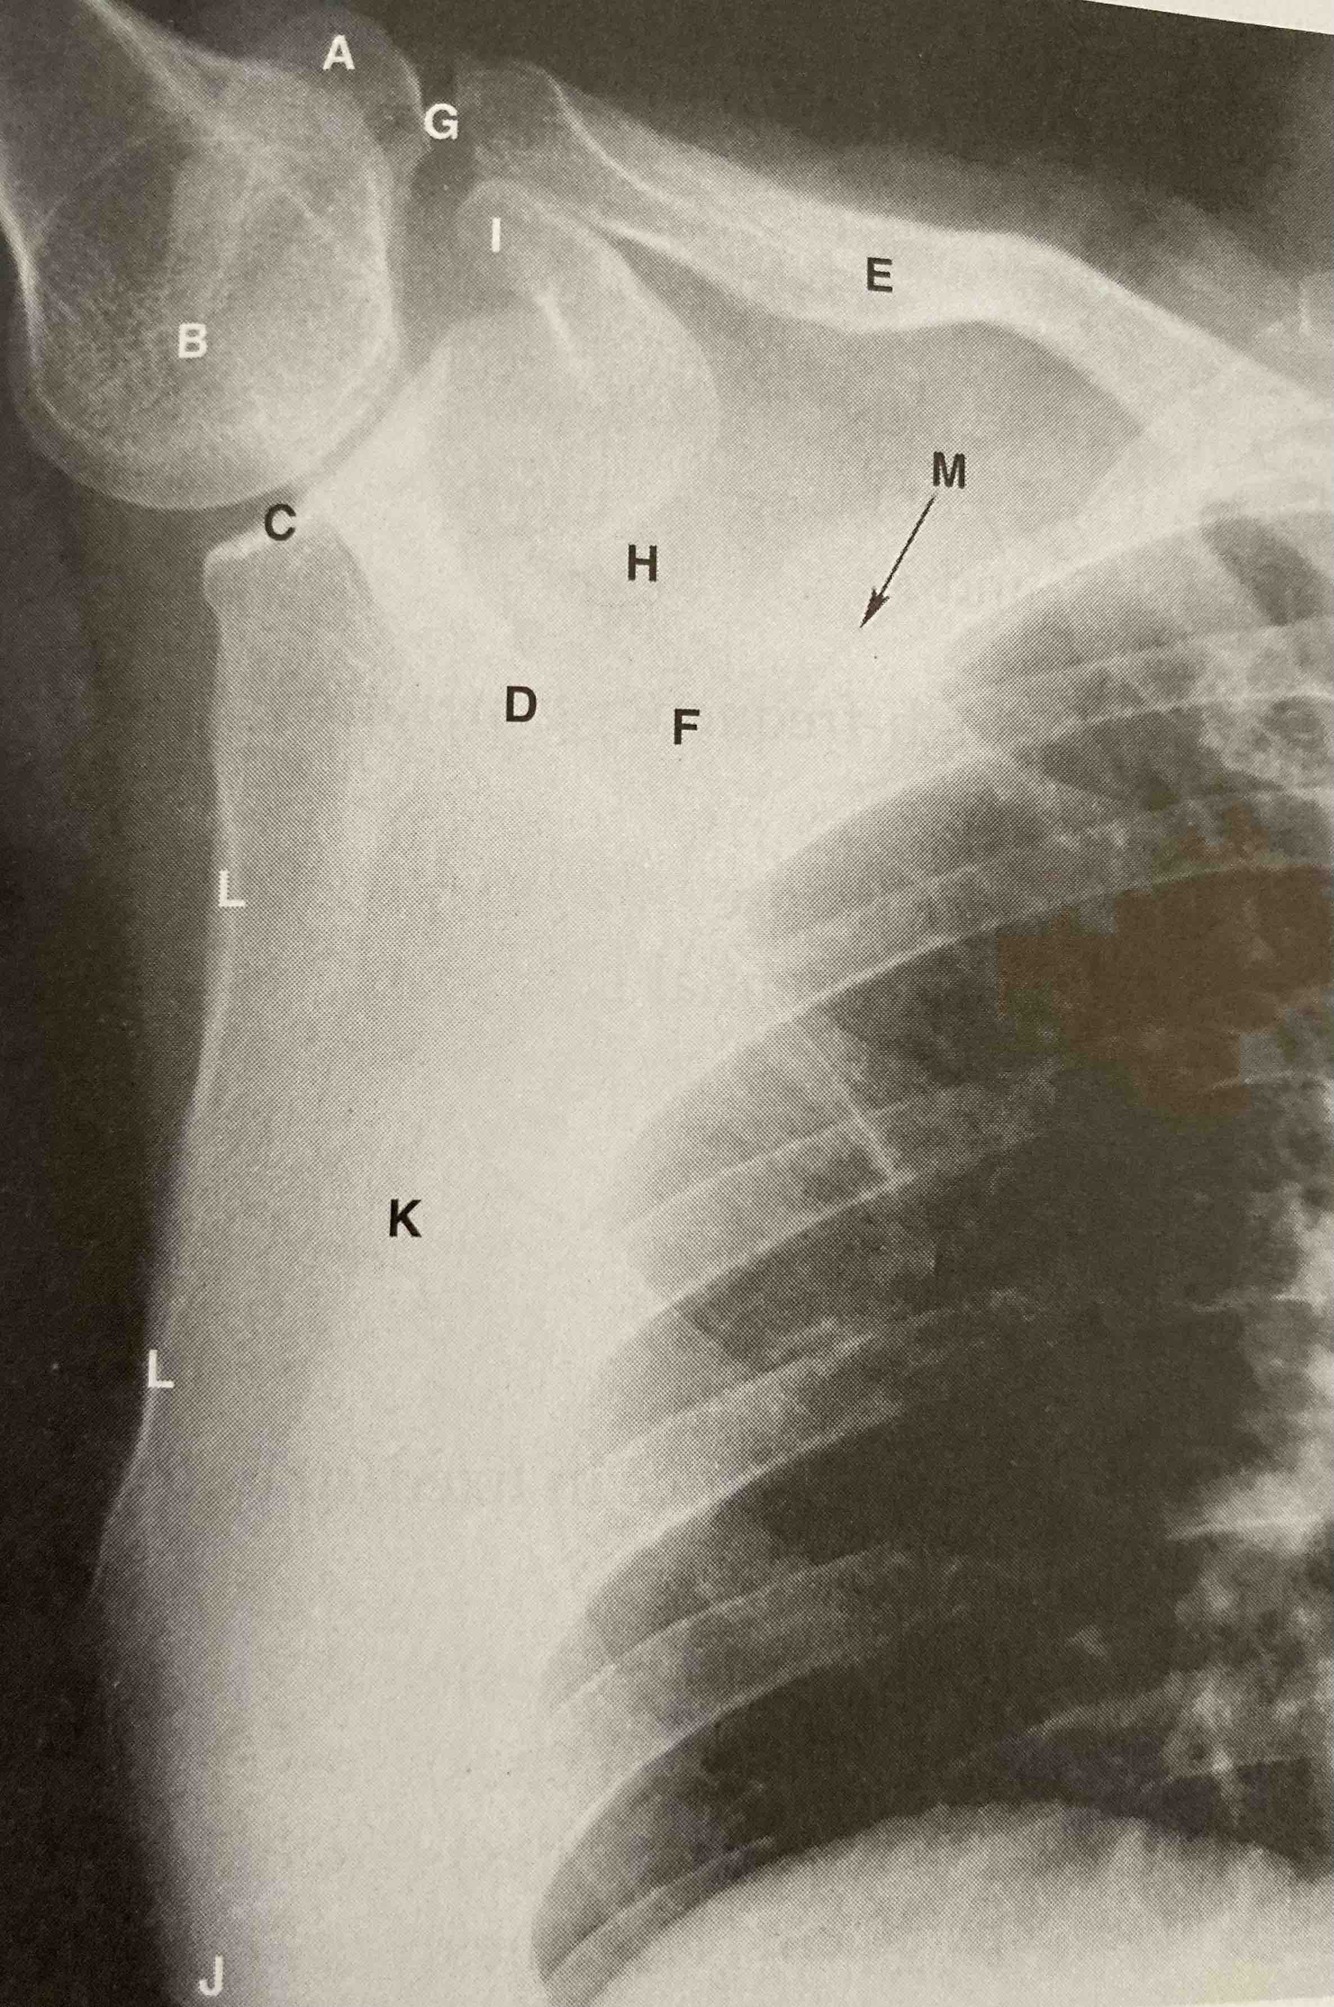

What is the structure indicated by the letter A in Figure below?

• Greater tubercle

• Coronoid process

• Coracoid process

• Acromion process

A

Acromion process

Which of the following indicates the glenoid cavity seen in Figure below?

• B

• C

• H

• M

C